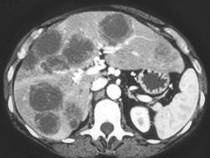

问题 男,54岁,患者一年前行结肠癌手术,癌胚抗原增高,影像检查如图,最可能的诊断是 ( )

选项 A.多发结节性肝癌 B.结肠癌肝转移 C.多发性肝脓肿 D.多发性肝囊肿 E.肝淋巴瘤

答案 B